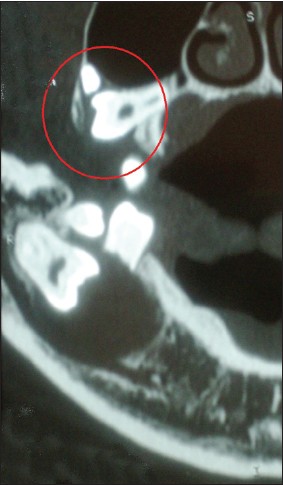

| Figure 4: CT image shows maxillary radiolucent lesion surrounding the right impacted third molar

Click here to view |